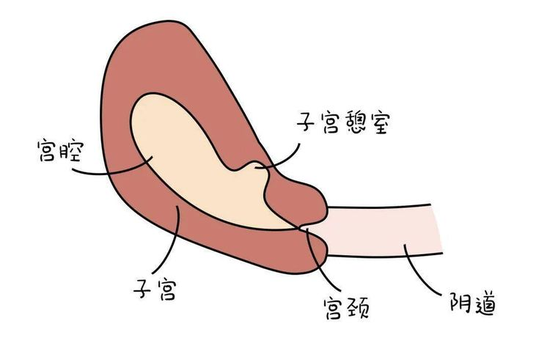

很多人在买房后都会试图扩大它的使用面积,让整个房子物尽其用。可是如果胎儿居住的子宫被扩建,多出一个被称作“憩室”的小房间,这就属于“违章建筑”了,它带来的危害和隐患也是不言而喻的。

妇产科医生介绍:剖宫产切口憩室是指子宫下段剖宫产术后的子宫切口由于子宫位置、缝合技术、感染等原因致愈合缺陷,在切口处形成一个与宫腔相通的憩室(或称为凹陷、假腔),由于憩室下端瘢痕的活瓣作用阻碍了经血的引流,积聚于憩室内,导致经期延长、淋漓不尽、经间期出血、痛经、甚至不孕等。严重影响妇女的身体健康和生命质量。